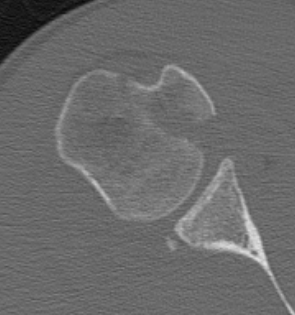

CT

Lesser tuberosity can become overgrown